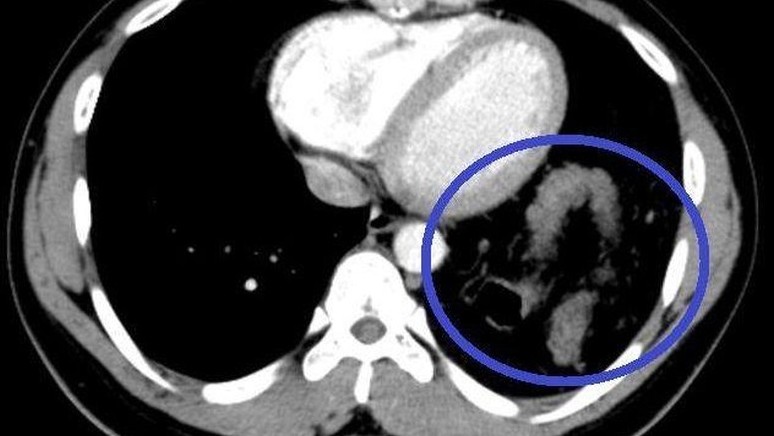

Phẫu thuật thành công khối u trong lồng ngực nặng 2kg tại Kon Tum

Ngày 7/6, Bệnh viện đa khoa tỉnh Kon Tum cho biết, cơ sở này đã phẫu thuật cho một bệnh nhân, cắt bỏ thành công khối u trung thất (khối u trong lồng ngực) với kích thước lớn 20x10cm, nặng 2kg.